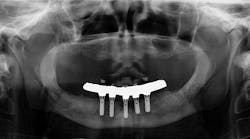

A PATIENT WHO RECENTLY MOVED TO THE AREA came in for a comprehensive exam and assessment. He had a lower fixed hybrid prosthesis put in more than five years ago that needed removal badly due to the amount of debris, plaque, and tartar that had accumulated underneath it (figure 1). Unfortunately, right away, there were two issues that challenged what normally would have been a straightforward removal:

Figure 1